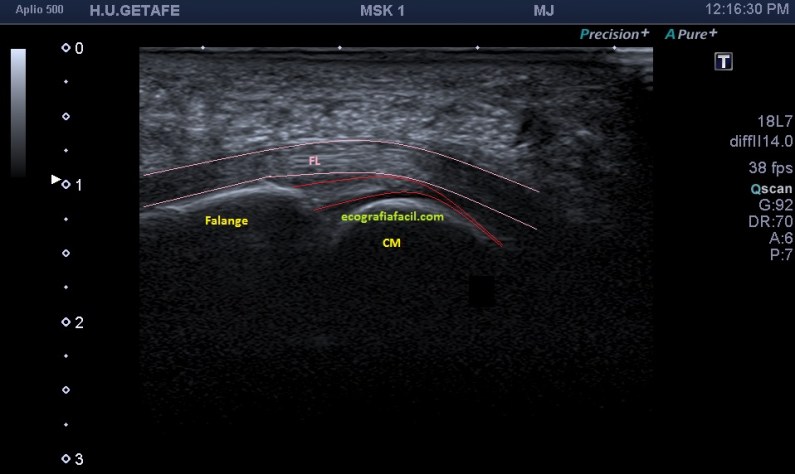

Anatómicamente la placa plantar es una estructura fibrocartilaginosa altamente resistente debido al colágeno tipo 1. Ecográficamente, está entre el flexor del dedo y la cabeza del metatarsiano y su aspecto es hiperecogénico, ocupando el espacio que va desde el cuello del metatarsiano hasta la porción distal y plantar de la falange articular con el metatarsiano. Imagen 3 y 4, normalidad ecográfica. Imagen 5, imagen patológica.

Estudiamos y demostramos la lesión o la normalidad en dos proyecciones, imagen 6, eje largo y eje corto de la zona y podemos comparar siempre con el lado contralateral, previsiblemente sano, dicho todo este conglomerado de ideas…las imágenes: